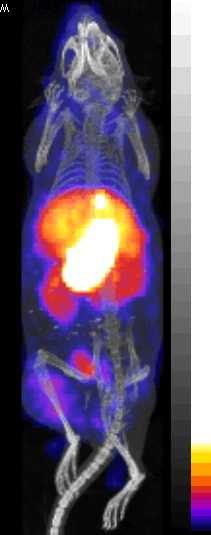

[18F]NaF Bone Scanning